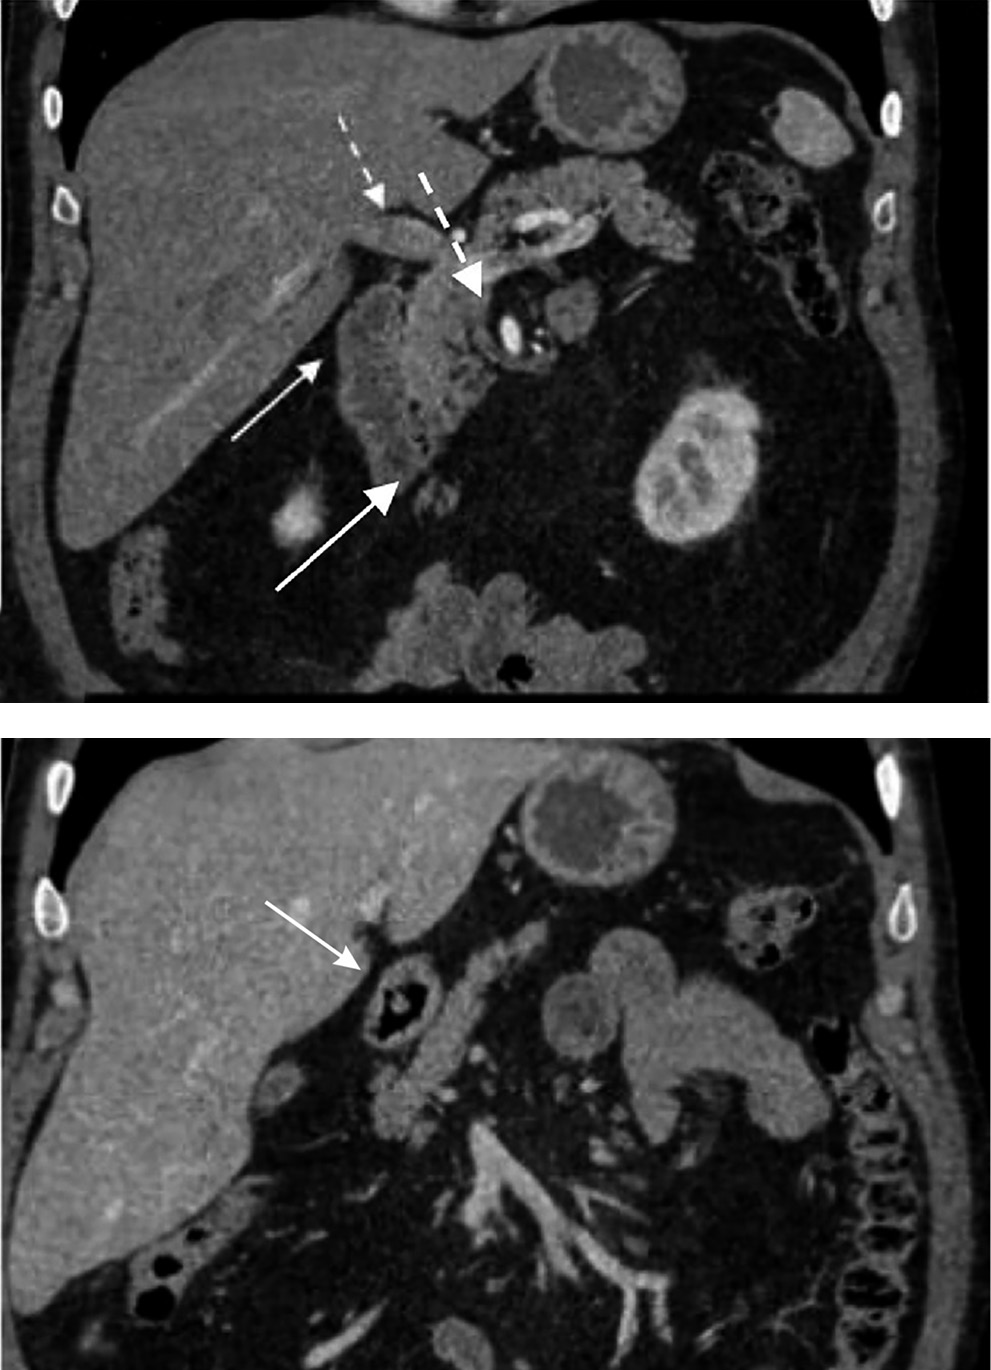

Рис. 6. Пациентка П., 29 лет. Грыжа большого сальника

На рис. 6 представлены томограммы пациентки П., 29 лет, выполненные во время приступа интенсивных абдоминальных болей. С помощью КТ обнаружены признаки грыжи большого сальника. Любопытно отметить, что болевой синдром регрессировал самостоятельно, и от хирургического лечения больная отказалась.